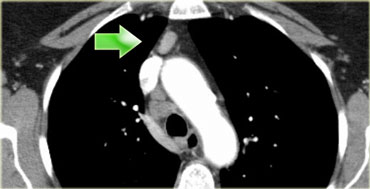

3. Hạch trước mạch máu và trước cột sống

3A: trước mạch máu hoặc

3B: sau thực quản.

Hạch nhóm 3 không tiếp cận được qua nội soi trung thất.

3P: có thể tiếp cận được qua siêu âm nội soi.

Hạch ở phía trước mạch máu – 3A (mũi tên)